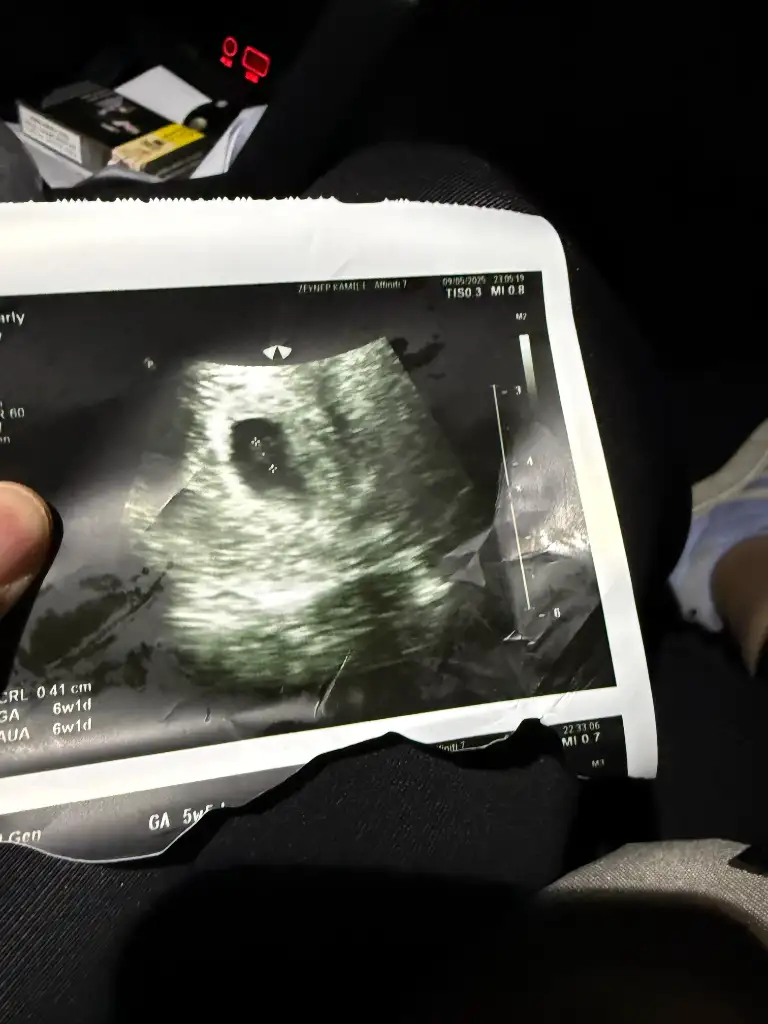

merhabalar banada tahminde bulunur musunuz 8+3 karından ulturason

Erkek bence plasenta yerine göre yorumladım sağlıkla gelsinOglusannesi banada yorum yapar mısınız

Çok teşekkür ederimErkek bence plasenta yerine göre yorumladım sağlıkla gelsin